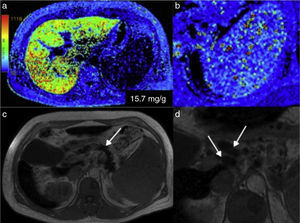

Steatosis quantification in color cartographyLiver fat quantification can also be carried out through cartography or a color map. It provides rapid visual appreciation of the existence of steatosis and the measurements are made directly on the image (Figure 7a, b, and c).

Color maps in 3 patients with different steatosis grades: a) patient with normal fat content: the dark blue of the liver corresponds to the lower part of the colorimetric scale and to a quantification below 6% (normal); b) in this patient the light blue is higher on the scale and the fat content is increased to an average 17%; c) the image in the third patient assigned green to the liver, which is indicative of a high fat content and was quantified at 33%.

The different colors of the map correspond to the distribution and intensity of the infiltrate that can be diffuse or regional (“geographic steatosis” or “in patches”), or even be present in a focal lesion, such as occurs in lipomas and some adenomas and hepatocellular carcinomas.

Cartography facilitates the analysis of fat content by comparing the colors of the colorimetric bar that is attached to the image. In our equipment, dark blue tones correspond to the lowest lipid concentration. Light blue and green tones indicate larger quantities of infiltrate, and yellow and red tones appear in the highest concentrations. The cartography image covers the entire circumference of the abdomen, and thus the subcutaneous fat and the peritoneal and perirenal spaces are also highlighted in red tones.

To quantify the liver infiltrate, the radiologist utilizes electronic devices that can choose the regions in which the percentage of the existing fat is to be calculated. The presence of fat within a focal lesion of the liver aids in its characterization (Figure 8).

Liver adenoma with fat. a) The T1 sequence shows 3 small focal lesions in segments 7 and 8 of the liver. The color map for quantifying fat shows that 2 of them have blue tones in the center (b), in which the lipid concentration was 37 and 19%, respectively (c). The histologic diagnosis was HNF1 adenoma.